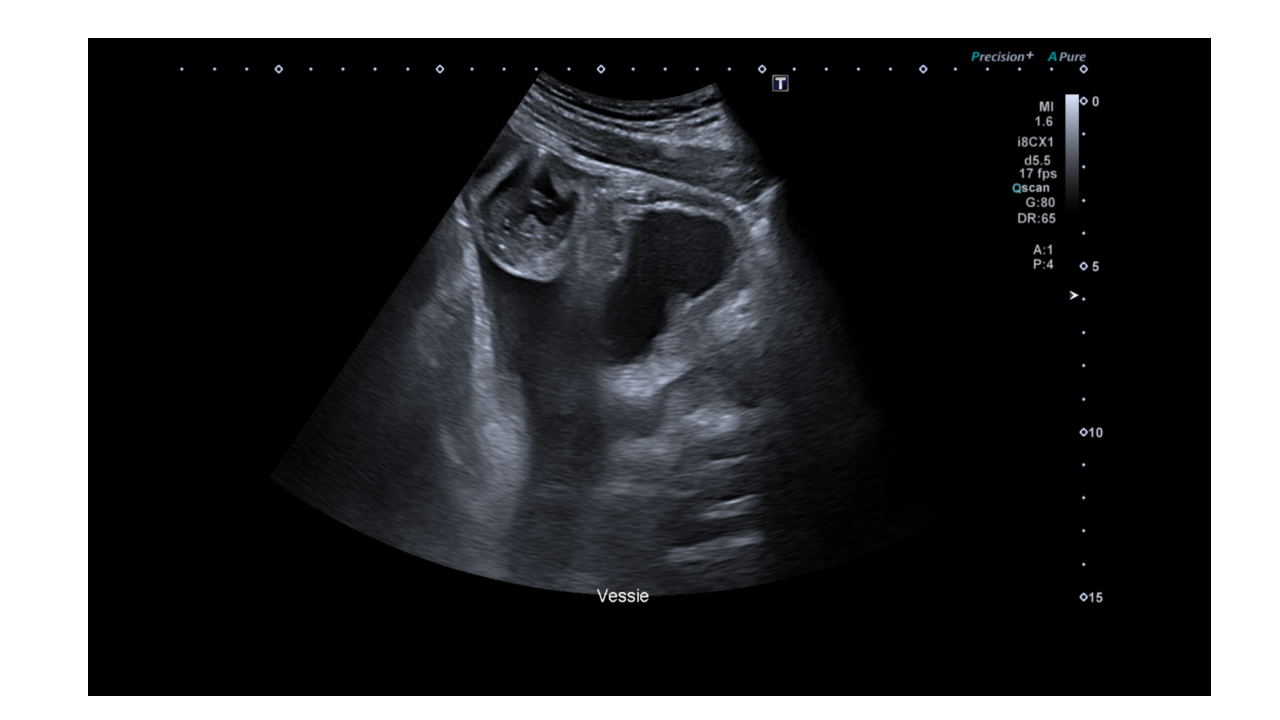

Une échographie vésico rénale pour dysurie chez un patient suivi pour sa prostate est réalisée par une manipulatrice en radiologie dans le cadre d'un protocole de coopération en échographie.

Apres avoir exploré les reins, la prostate (en sus pubien) et la vessie, son attention se porte sur cette image, à droite de la vessie sur une coupe sagittale, et sur l'ascite dans le cul de sac de douglas.

Le patient présente des douleurs abdominales, un balayage complémentaire est alors réalisé avec une fréquence d’émission augmentée pour mettre en évidence cette structure.